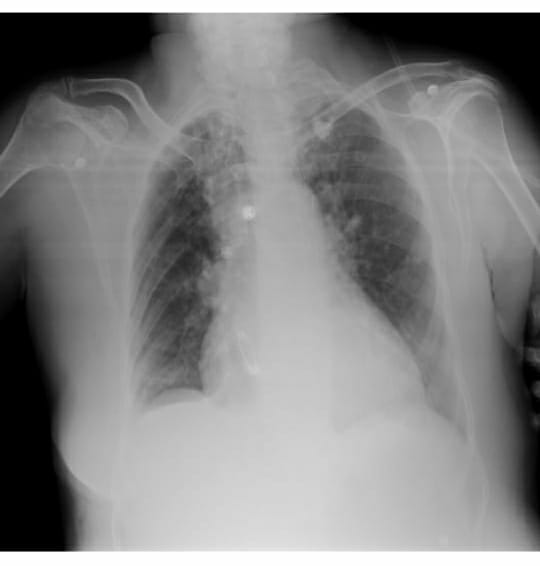

Chronic pancreatitis with pseudocyst

Acute infective peri pancreatic fluid collections

Left pleural effusion with basal atelectasis in left lung

Left pneumothorax with secondary to broncho pleural fistula